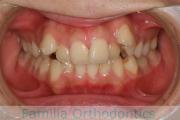

No.23V-061

- 主な症状:

- 叢生

- その他の症状:

- 上下顎前突

- 年齢:

- 23歳

- 性別:

- 女性

- 抜歯部位

- 上:

- 44

- 下:

- 主な使用装置:

- FEA 022

- 治療にかかった費用:

- 88万円

でこぼこを綺麗に並べたいということで来院されました。上下左右から小臼歯を抜歯して、マルチブラケット法を2年半、30回程度通院していただいて行いました。

かなり強い叢生(でこぼこ、凹凸、ガタガタ)のため、保定をしっかりしないと後戻りのリスクが高いケースといえます。

- ≫治療前

-